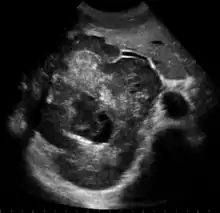

تصوير بالموجات القوق الصوتية يوضح وجود ورم كبدي كبير الفص الايمن للكبد بالكامل